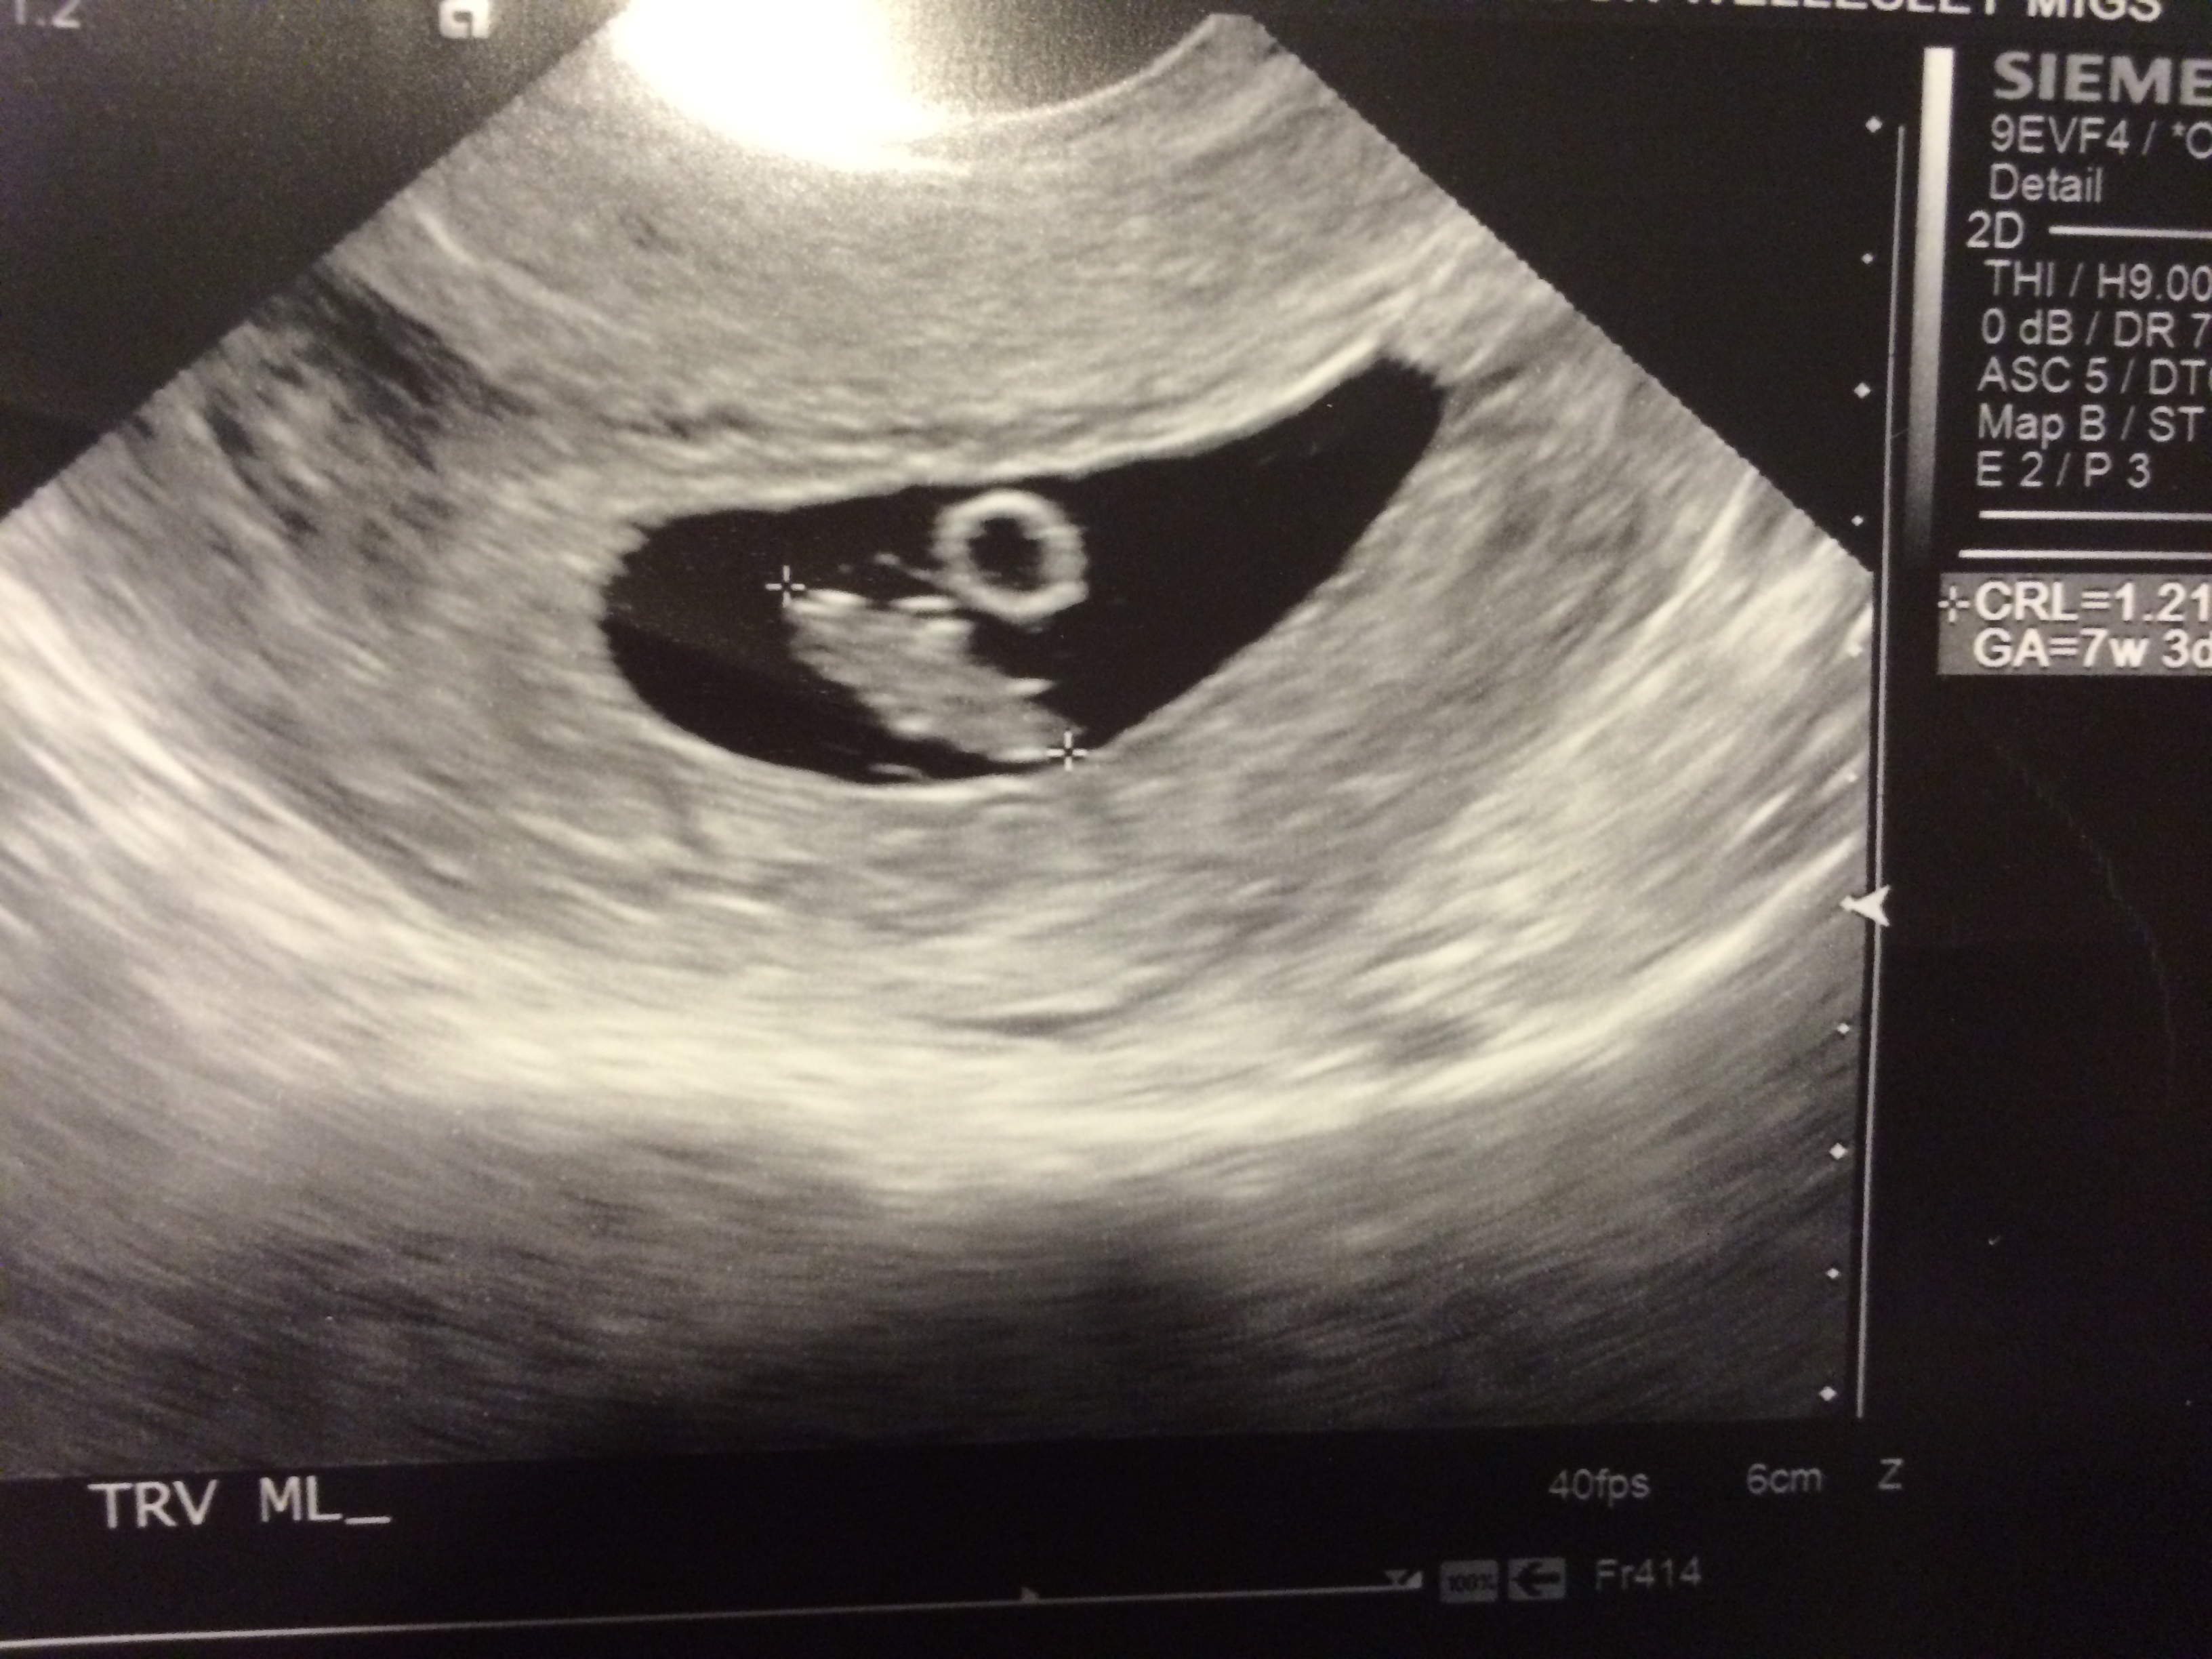

I logged in this morning to read the report of my first ultrasound from the RE done on 5/1.

Everything was good except for the last line "A 1.2 x 0.5 x 1.3cm subchorionic hematoma is identified." They didn't say anything during my US.

Of course I turned to Dr. Google and now i'm a nervous wreck. I checked my ultrasound pics again and really couldn't see it, unless it's the thing on the left side of the gestational sac? I've had no bleeding or spotting so far. I will call the RE office in a bit to ease my mind.